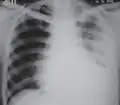

Fibrothorax

| Fibrothorax on chest x-ray | |

Fibrothorax is a medical condition characterised by severe scarring (fibrosis) and fusion of the layers of the pleural space surrounding the lungs resulting in decreased movement of the lung and ribcage.[1] The main symptom of fibrothorax is shortness of breath. There also may be recurrent fluid collections surrounding the lungs. Fibrothorax may occur as a complication of many diseases, including infection of the pleural space known as an empyema or bleeding into the pleural space known as a haemothorax.[2]

Fibrosis in the pleura may be produced intentionally using a technique called pleurodesis to prevent recurrent punctured lung (pneumothorax), and the usually limited fibrosis that this produces can rarely be extensive enough to lead to fibrothorax.[3] The condition is most often diagnosed using an X-ray or CT scan, the latter more readily detecting mild cases. Fibrothorax is often treated conservatively with watchful waiting but may require surgery. The outlook is usually good as long as there is no underlying pulmonary fibrosis or complications following surgery. The disease is highly uncommon.

Diagnosis

A fibrothorax can typically be diagnosed by taking an appropriate medical history in combination with the use of appropriate imaging techniques such as a plain chest X-ray or CT scan.[3] These imaging techniques can detect fibrothorax and pleural thickening that surround the lungs.[7] The presence of a thickened peel with or without calcification are common features of fibrothorax when imaged.[3] CT scans can more readily differentiate whether pleural thickening is due to extra fat deposition or true pleural thickening than X-rays.[3]

If a fibrothorax is severe, the thickening may restrict the lung on the affected side causing a loss of lung volume.[7] Additionally, the mediastinum may be physically shifted toward the affected side.[3] A reduction in the size of one side of the chest (hemithorax) on an X-ray or CT scan of the chest suggests chronic scarring.[6] Signs of the underlying disease causing the fibrothorax are also occasionally seen on the X-ray.[6] A CT scan may show features similar to those seen on a plain X-ray.[7] Lung function testing typically demonstrates findings consistent with restrictive lung disease.[6]

Extensive left-sided fibrothorax

Chest radiograph displaying inhomogeneous opacification of the left half of the chest that is fibrothorax